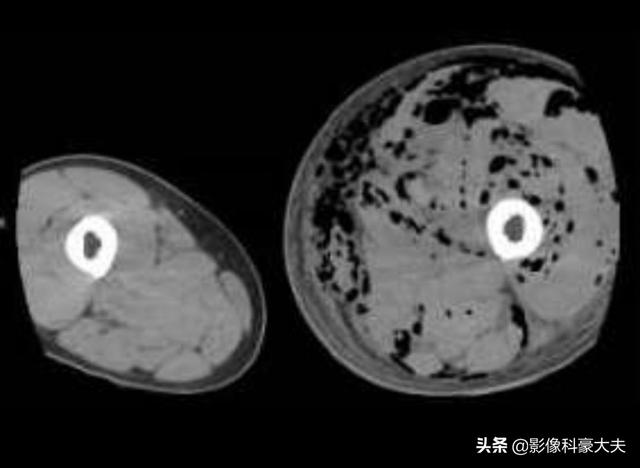

下の写真は、32歳で血糖値が30台だった患者がクレブシエラ菌に感染し、肺膿瘍、肝膿瘍、下肢感染症を引き起こしたものである:

左足は目に見えて腫れており、筋肉の隙間に黒い泡がたくさんある。このような重症感染症の患者は死亡率が高い!